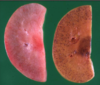

Glomerular amyloidosis

Lugol’s iodine stain on fresh tissue (congo red for histo)

glomerular amyloidosis

DDX?

STain used?

glomerular amyloidosis

congo red- fluoresce green with UV light